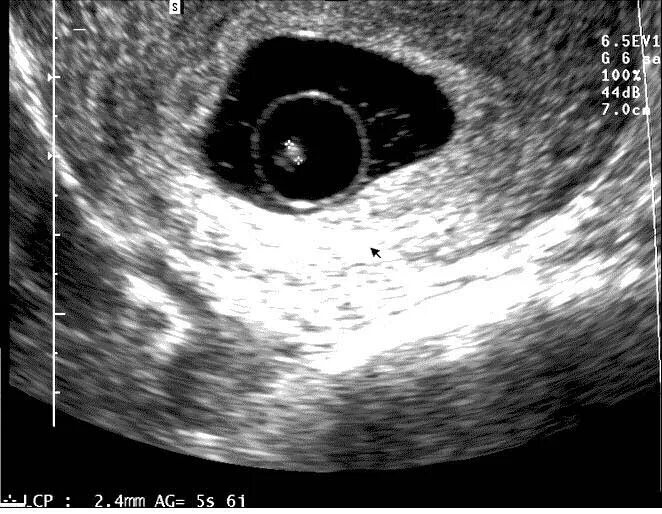

6 недель беременности как выглядит эмбрион